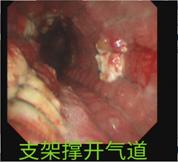

介入手术如期举行,正如吴主任所料,患者根本不能躺下,张绿秀麻醉师只能让患者坐着实施诱导麻醉,麻醉后上官主任在团队娄希贤、朱梦楚、颜晗晗等医生的协作下快速插入硬质支气管镜建立气管通道后,立即实施气道内肿瘤圈套切除术,术中患者血氧饱和度一度下降,在打通一条细小通道后立即置入导丝,成功放置一个覆膜支架,支架释放后患者血氧饱和度立即上升,手术取得圆满成功。

手术后当天患者就能平卧睡觉,第2天就能下床活动。之后转放疗科完成放疗后,患者病情得到了有效的控制,已经能够活动自如,目前已经平安出院,即将回到回到阔别已经的安徽老家。